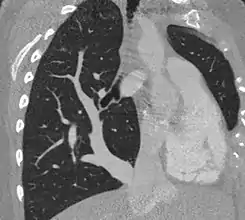

El síndrome de la cimitarra, también conocido como síndrome de drenaje venoso anómalo del pulmón derecho, es una enfermedad congénita inusual que consiste en un mal drenaje de las venas pulmonares derechas a la vena cava inferior, aurícula derecha, que con frecuencia se asocia a hipoplasia del pulmón derecho y de la arteria pulmonar derecha. También se han descrito malformaciones bronquiales, dextrocardia e irrigación arterial anómala de la aorta hacia el pulmón derecho.

![]() Síndrome de la cimitarra.TAC torácico | ||

Así mismo, su imagen radiológica es clave, ya que recuerda a la de un sable turco en la radiografía de tórax simple. Suele estar acompañado por hipoplasia pulmonar derecha y dextrocardia. Su imagen radiológica corresponde a la visualización de un gran vaso venoso (drenaje de las venas pulmonares) anómalo que recorre la silueta cardíaca derecha para drenar en la vena cava inferior por arriba o por debajo del diafragma.